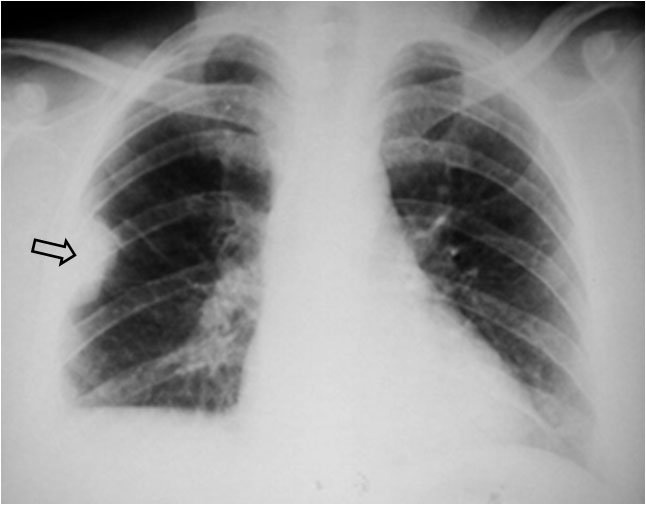

SIGNO DE LA JOROBA DE HAMPTON

Opacidad en cuña con base de contacto pleural, generalmente sin broncograma aéreo, que corresponde a infarto pulmonar. Aunque con frecuencia se localiza en el seno costofrénico lateral, puede encontrarse en otras localizaciones. La fotografía muestra una radiografía PA de tórax donde se observa una joroba de Hampton en el campo medio pulmonar derecho (flecha).